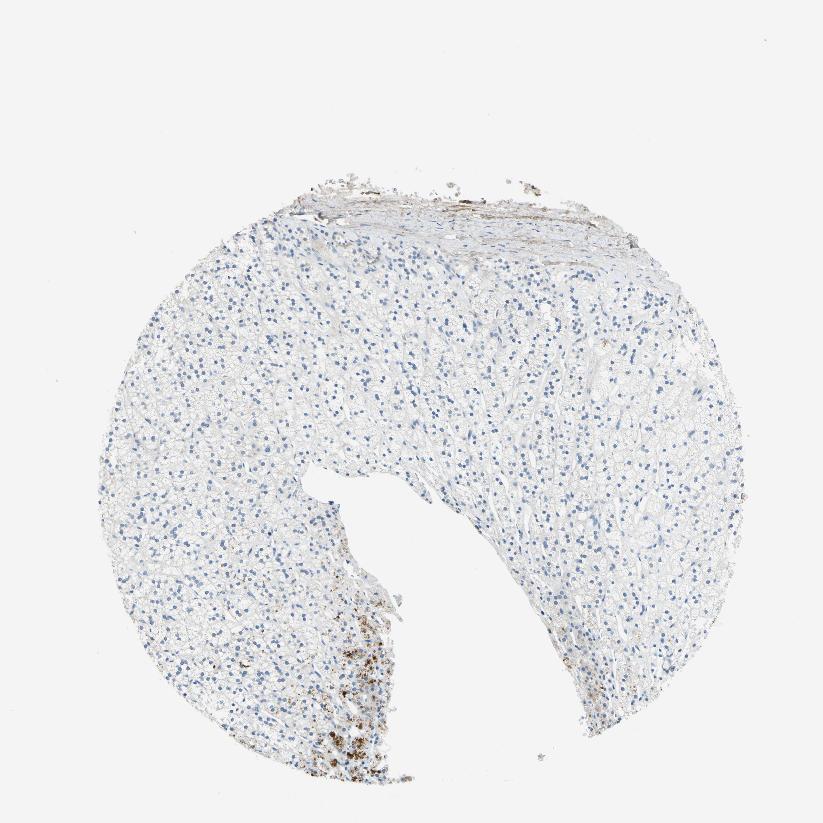

ADRENAL GLAND - Antibody stainingi

Antibody staining in the annotated cell types in the current human tissue is reported as not detected, low, medium, or high, based on conventional immunohistochemistry profiling in selected tissues. This score is based on the combination of the staining intensity and fraction of stained cells.

Each image is clickable and will lead to virtual microscopy that enables deeper exploration of all samples and also displays staining intensity scores, fraction scores and subcellular localization as well as patient and tissue information for each sample.

Antibody HPA013132

Glandular cells Medium